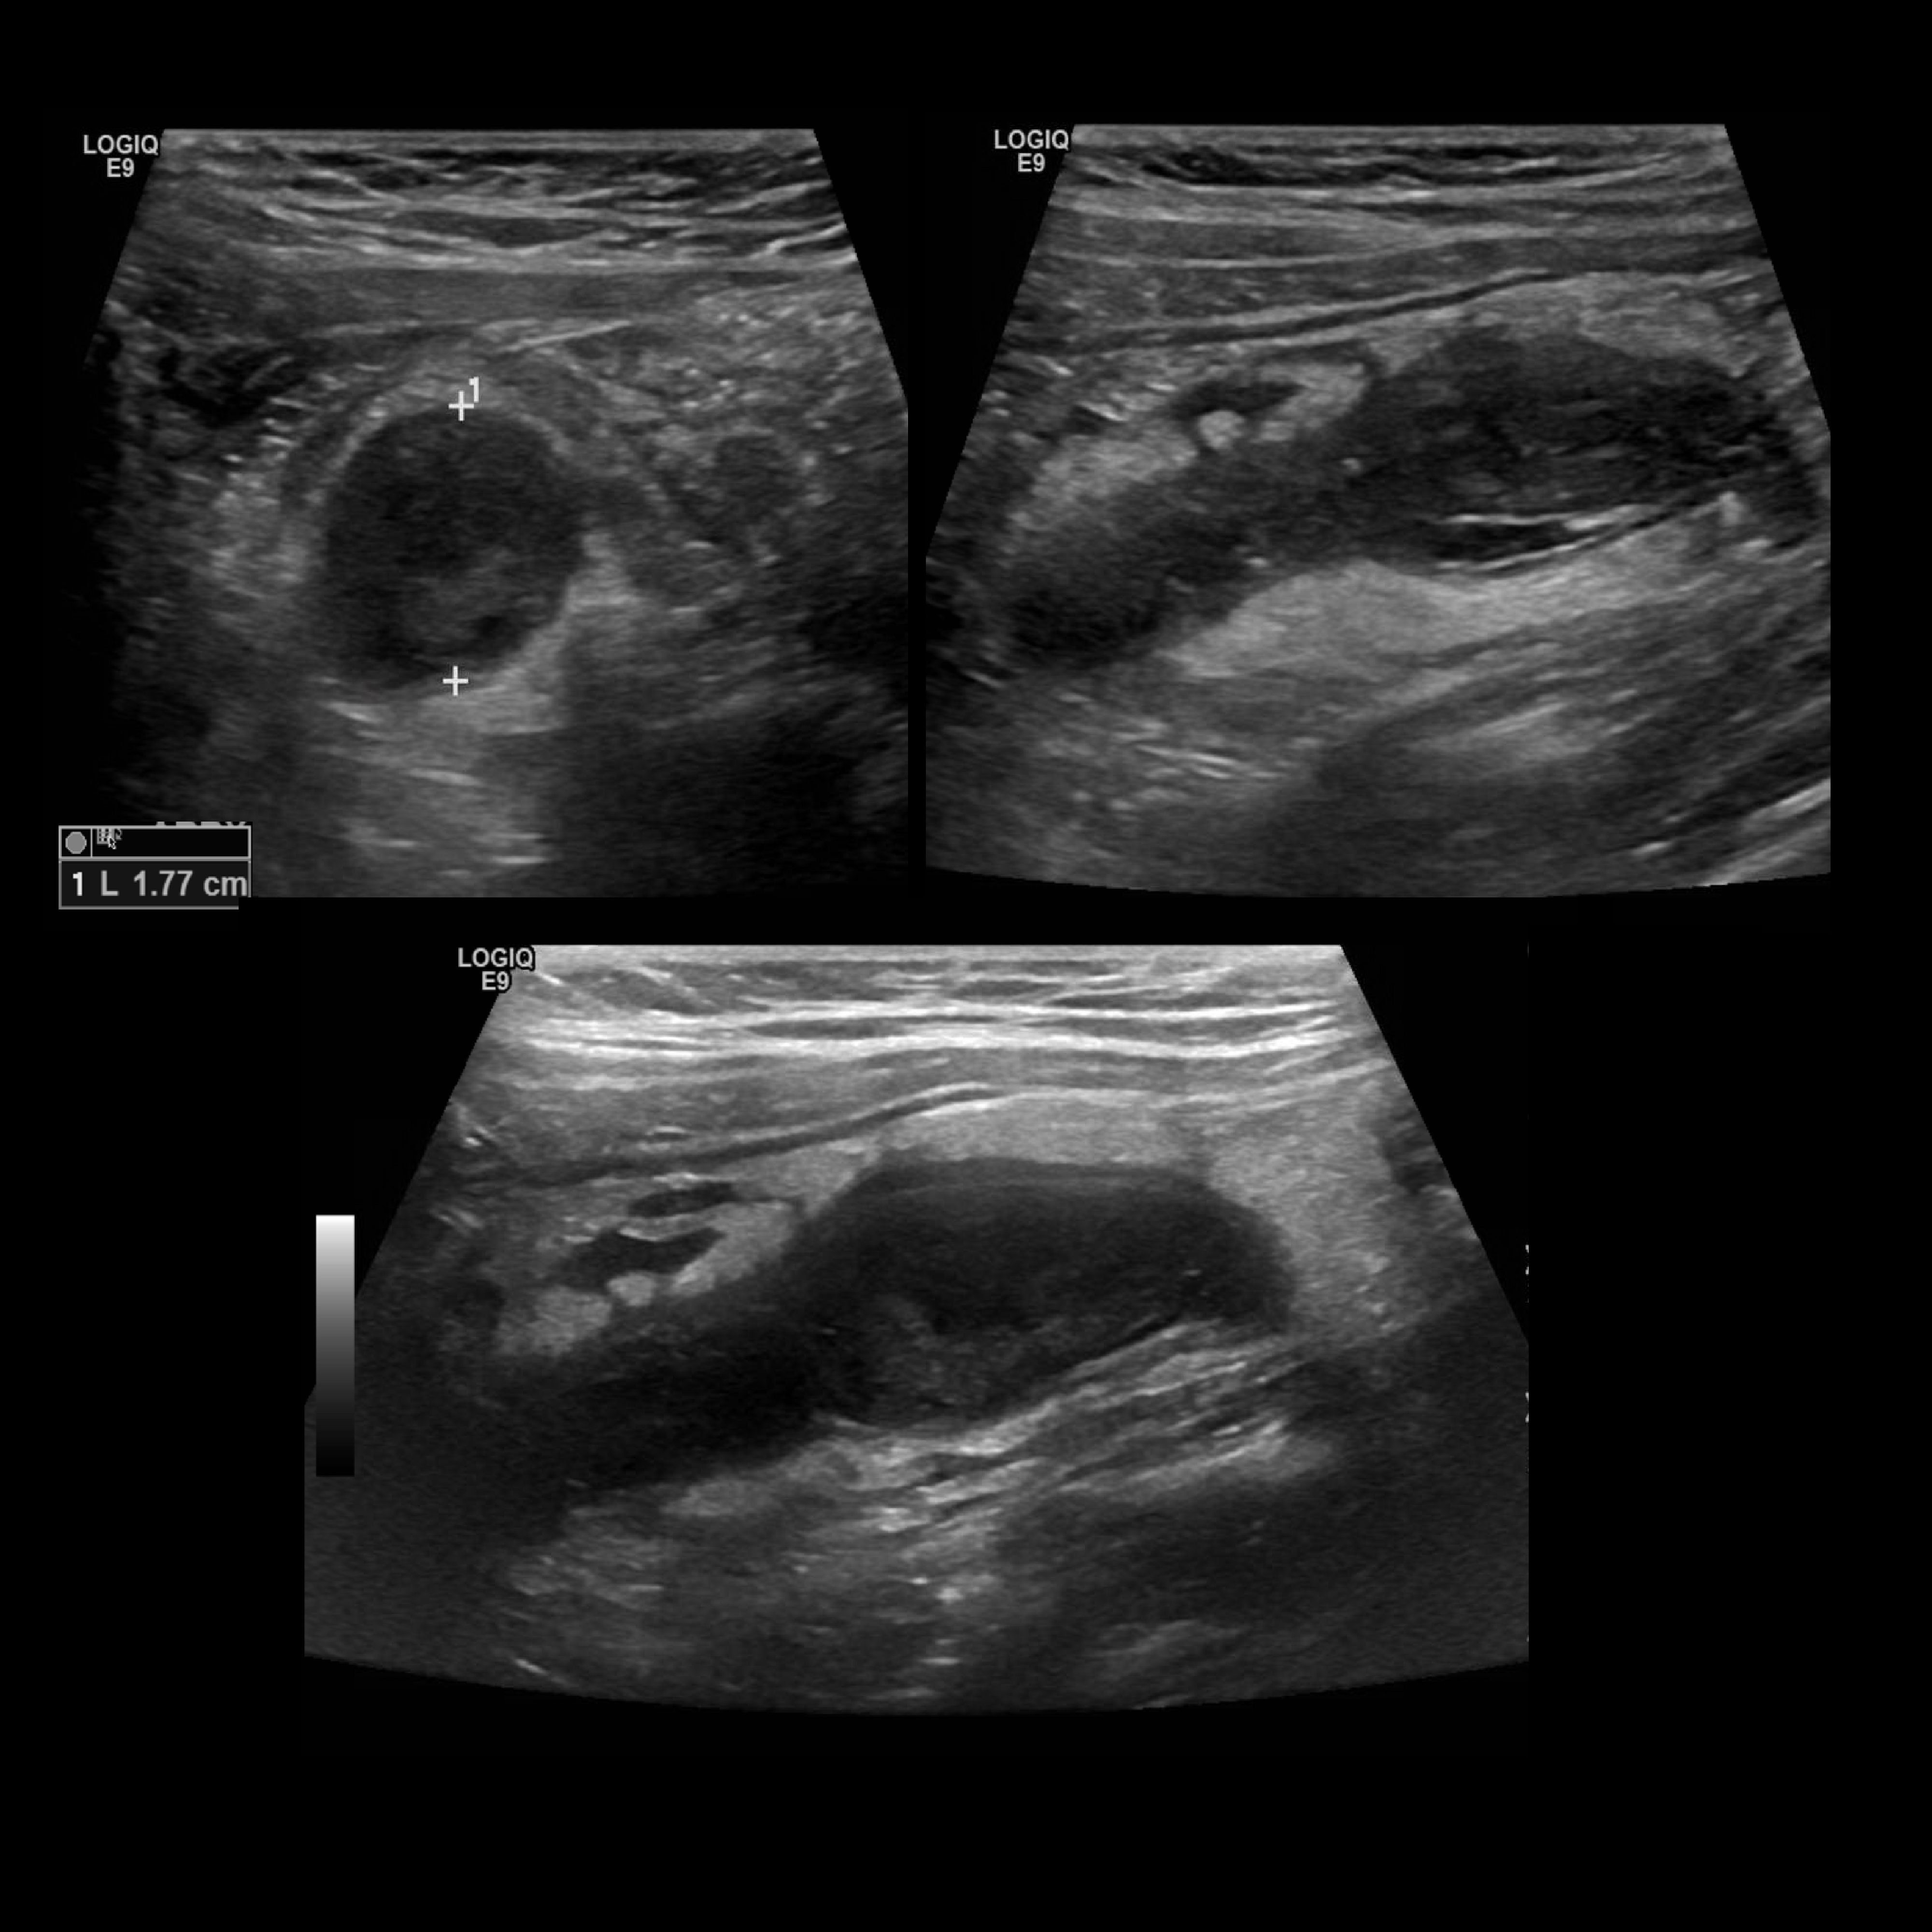

Appendicitis 6

Perforated appendicitis with complex fluid/abscess formation.